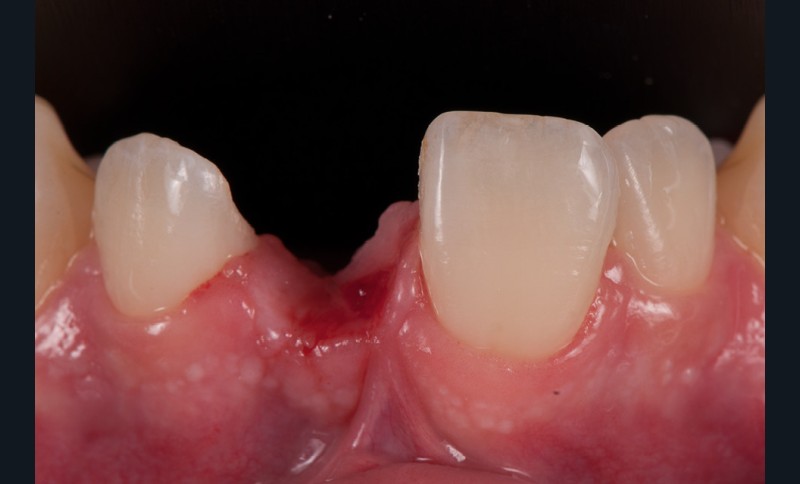

- Il faut aussi anticiper la nécessité d’une greffe de conjonctif au niveau du futur nouveau pontique compte tenu de la perte de tissus (effondrement en vestibulaire de la crête)

- De même, il faut anticiper le mode de temporisation en se servant de cet ancien bridge collé en temporisation (assemblé au CVIMAR avec un peu de glycérine pour en faciliter la dépose) pendant la phase de cicatrisation parodontale (12 semaines post-opératoires environ), puis la réalisation d’une gouttière avec une centrale du commerce en résine à l’issue du temps de maturation parodontale pour la préparation…